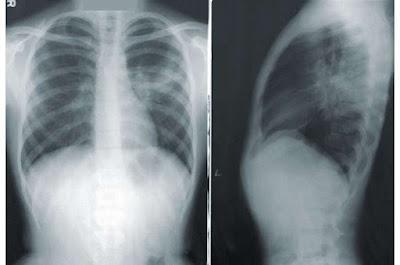

Como su nombre lo indica, sulbactam-durlobactam combina dos fármacos. El sulbactam ha sido aprobado para su uso desde 1986, pero el durlobactam es nuevo y aún no ha obtenido la aprobación, sin embargo los hallazgos han llevado a un comité unánime de expertos a recomendar a la Administración de Alimentos y Medicamentos (FDA) que apruebe el nuevo fármaco, que podría estar disponible este verano para combatir la cepa de neumonía, a menudo mortal, conocida como complejo Acinetobacter baumannii-calcoaceticus resistente a los carbapenems (ABC ), típicamente adquiridos en hospitales. Desafortunadamente, sulbactam-durlobactam no es el tipo de antibiótico de amplio espectro que podría resultar efectivo para tratar una amplia variedad de infecciones resistentes a los antibióticos, pero es muy bueno para tratar esta particularmente peligrosa, y eso es una victoria significativa.